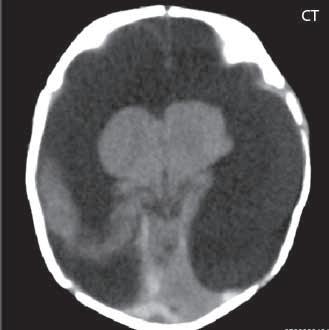

Obr. I.1.8a Dandy-Walkerova malformace, rozšířená IV komora (tvar klíčové dírky)

Obr. I.1.8b Dandy-Walkerova malformace, rozšířená IV komora široce komunikující s cisterna magna, hypotrofie mozečku (snímky zapůjčeny z archivu prim doc MUDr M Mechla, Ph D, MBA)

Obr. I.1.8c Dandy-Walkerova malformace, rozšířená IV komora široce komunikující s cisterna magna, hypotrofie mozečku (snímky zapůjčeny z archivu prim doc MUDr M Mechla, Ph D, MBA); stejný pacient jako na obr I 1 8b

Obr. I.1.8d Dandy-Walkerova malformace, rozšířená IV komora široce komunikující s cisterna magna, hypotrofie mozečku, vysoký úpon tentoria (šipka) (snímky zapůjčeny z archivu prim doc MUDr M Mechla, Ph D, MBA); stejný pacient jako na obr I 1 8b, c

D-W malformace je charakterizována hypoplazií vermis mozečku, rozšířením IV. mozkové komory, která se často cysticky vyklenuje dorzálně a může imitovat arachnoidální cystu, rozšířením zadní jámy lební a vysokým úponem tentoria s confluens sinum nad lambdovým švem. Okcipitální kost může být vlivem tlakových změn remodelována, existují i případy s porušením její kontinuity a encefalokélou. Hydrocefalus pozorujeme v 80 %, častá je přítomnost dysgeneze corpus callosum, schizencefalie.

V současné odborné literatuře je nejčastěji užíván termín D-W spektrum, který snad nejlépe vyjadřuje velmi široké možnosti vrozených změn zadní jámy lební. Mezi tuto skupinu cystických malformací zadní jámy lební pak řadíme klasickou malformaci D-W a její varianty, mega cisterna magna, arachnoidální cystu zadní jámy lební a retrocerebelární vak (Blake’s pouch cysta). Zařazení malformace do určité klinické jednotky není někdy jednoznačné, proto je možná výhodnější a přesnější vycházet z přesného popisu zobrazených změn. Příčina D-W malformace není známa, nabízejí se dvě hypotézy: 1. nepropustná spodina IV. komory, eventuálně uzávěr nebo pozdní otevření otvorů, kterými proudí likvor ze IV. komory. 2. primární hypogeneze mozečku. Embryonální vývoj mozečku ze všech hlavních struktur mozku trvá nejdelší dobu, a proto je velmi vulnerabilní k různým patologickým příčinám po dlouhou dobu svého vývoje.

Zobrazení